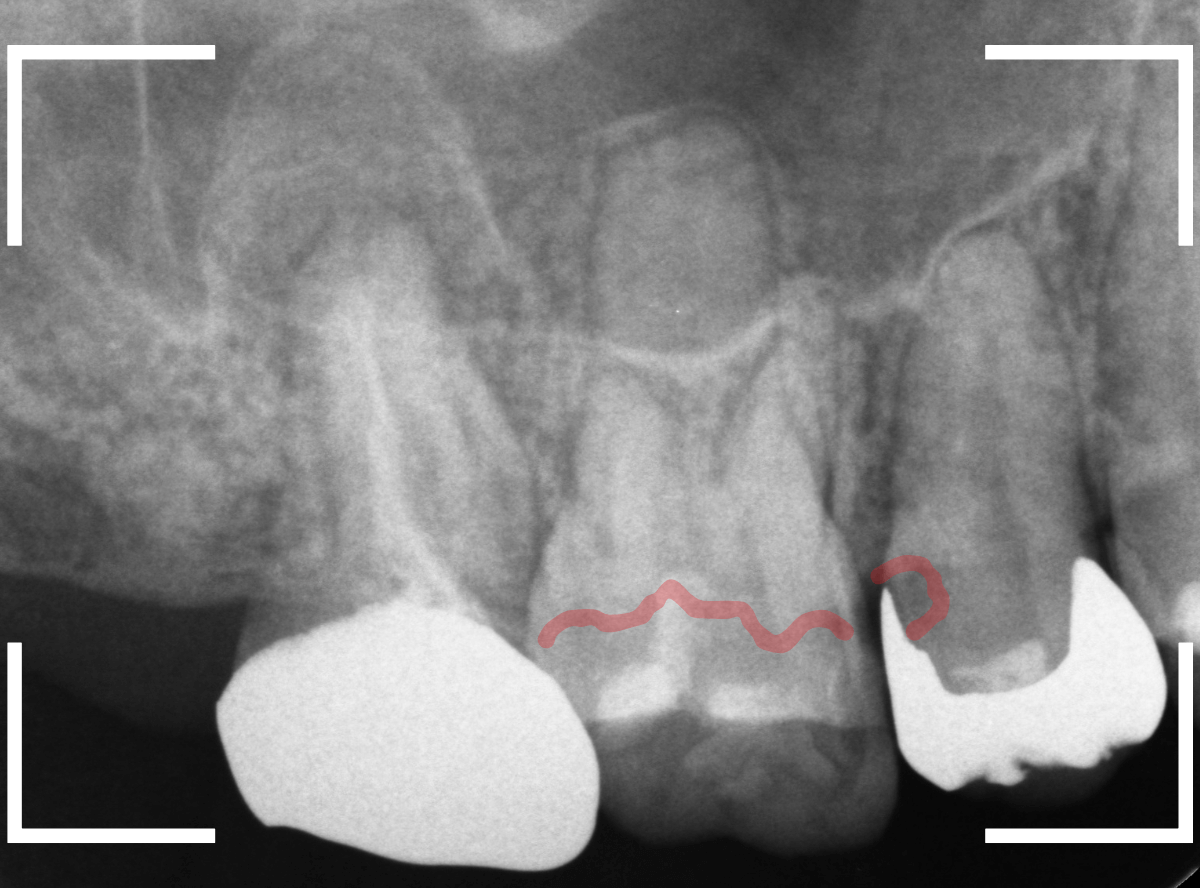

Case.17 レントゲンにはっきり写らないレジンの中の虫歯を削って調べる2

今回も、下の奥歯の虫歯を治療した例です。

特に症状はありませんが、以前に治療したレジンが劣化してすり減っているのと、少し中が黒く透けて見えて、虫歯になっているのが怪しいです。

青いラインが歯の神経です。

以前の虫歯が深めだったようで、レジンが深めにつめてあるのがわかります。

その下がうっすらと虫歯っぽい影になっています(赤いライン)。

虫歯になっているか微妙なラインですが、レジンも劣化していますので、患者さんにご説明して治療することになりました。

レントゲンで虫歯と思われる部分をレジンを除去しました。

見た目には虫歯かどうかはっきりわかりません。

う蝕検知液で染め出します。

うっすらと赤く染色されました。

レントゲン写真と同じく、レジンの下で静かに虫歯が進行し始めていたようです。

もともと深めの虫歯だった部分なので、早いうちに治療が進められてよかったです。

全てのレジンと虫歯を除去しました。

お薬をつめて、症状が出ないかしばらく経過観察します。

歯の外壁部分も薄くなってますので、レジンでは長期保存は難しいと思われます。

今回は、インレーで最終修復する予定です。